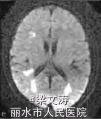

体温38.1℃,意识清楚,定向力、记忆力、计算力等高级皮质功能明显受损;脑神经阴性;四肢肌力V级,肌张力正常,腱反射(++),两侧对称;双侧巴氏征阴性,脑膜刺激征阴性。共济运动及感觉系统查体不能配合。全身浅表淋巴结未触及肿大,两肺未闻及干湿性啰音,心律齐,腹平软,肝脾肋下未触及,双下肢无水肿。血常规示三系减低:白细胞计数3.6 X10^9/L(参考范围:4.0 X 10^9/L一10.0×10^9/L),红细胞计数2.15×10^12/L(参考范围:4.00×10/L一5.50×10^12/L),血小板计数68×10^9/L(参考范围:100×10^9/L一300×109/L)],低蛋白血症[清蛋白28.5 g/L(参考范围:35.0一52.0g/L)];红细胞沉降率、肝肾功能及电解质均正常,维生素B、叶酸正常,3次血培养均阴性;艾滋病抗体阴性;抗核抗体、肿瘤标志物、自身抗体及抗中性粒细胞胞质抗体(ANCA)阴性,免疫球蛋白M轻度降低[0.28 g/L(参考范围:0.46—3.04 g/L)];乳酸脱氢酶[1 120 U/L(参考范围:135—225 U/L)]和血13:微球蛋白[3.7 mg/L(参考范围:1.0—2.5 zng/L)]明显增高。腰椎穿刺脑脊液检查示:压力150 illln H20(参考范围:80-180mmH20,1 mm H20=0.0098 kPa),白细胞计数7×10*6/L[参考范围:(0—10)X100/L],蛋白2.80 g/L(参考范围:0.10—0.25 g/L),氯离子:107 mmol/L(参考范围:120—130 mmol/L),糖3.5 mmol/L(参考范围:2.5~4.5 mmol/L);细胞学正常;IgG指数0.099;JCV—DNA阳性;单疱病毒、柯萨奇病毒、埃可病毒、巨细胞病毒等抗体阴性;墨汁染色阴性,细菌加真菌培养阴性。2.3影像学检查2009-12-25腹部CT提示脾脏偏大,2010-01-12复查腹部CT提示脾脏肿大、两侧肾上腺区团块影。2009-12-29颅脑MRI示两侧半卵圆中心、侧脑室旁多发病变009—12—24骨髓穿刺检查示有核细胞增生活跃,红系/粒系(G/E)=0.87:1;中性粒细胞增生(占40.4%),以中性中间阶段粒细胞为主;红细胞增生(占46.4%),以中晚幼红细胞为主;淋巴细胞比例下降;血小板计数较少,吞噬细胞增多,未见明显异常细胞,CD3、CD8、CD4、CD16、CD56均正常。

患者2009—12—27入住感染科,予头孢哌酮针及阿奇霉素针抗感染等治疗,病情无明显好转。2009—12—29行颅脑MPd检查示脑内多发脱髓鞘样病灶,于2010—01—06转入神经内科并行相关检查。根据该患者的临床和影像学特征,结合脑脊液中JCV的DNA序列检测以及骨髓穿刺病理活检结果,诊断为弥漫大B细胞淋巴瘤并发PML可能。虽经退热、补液,纠正贫血、低蛋白血症等积极治疗,但患者病情仍迅速进展,于2010—01—28凌晨出现呼吸、心搏停止,予气管插管、心肺复苏等积极抢救治疗后呼吸、心搏恢复。患者自动出院1 d后死亡,家属拒绝尸检

本例患者表现为视觉障碍、认知功能减退和精神行为异常等典型的PML症状,颅脑MRI检查符合典型的PML影像学表现;脑脊液中检测到JCV的DNA序列,病理活检证实弥漫大B细胞淋巴瘤侵犯骨髓,并且缺少其他感染或肿瘤的依据。因此,本例患者诊断为弥漫大B细胞淋巴瘤并发PML。PML患者通常处于免疫抑制状态,在此基础上需要与其他颅内多发病灶鉴别,如中枢神经系统血管炎、原发性中枢神经系统淋巴瘤以及脑弓形体病等。本例患者病史和实验室检查以及颅脑MRI表现均不支持以上疾病的诊断。目前,针对PML尚无特异的治疗措施,PML患者的预后极差,临床需引起足够的重视。当存在免疫缺陷或免疫抑制的患者出现典型的视觉障碍、认知功能改变、肌无力等症状时,应考虑本病的可能。本例患者虽经积极对症治疗,但患者病情仍迅速进展、恶化。因此,在病程早期行颅脑MRI检查以及腰椎穿刺脑脊液检测JCV的DNA序列,均有助于本病的诊断,必要时可行脑组织活检。明确诊断后应立即开始免疫重建治疗,抑制脱髓鞘的继续进展;同时避免医源性PML也非常重要。